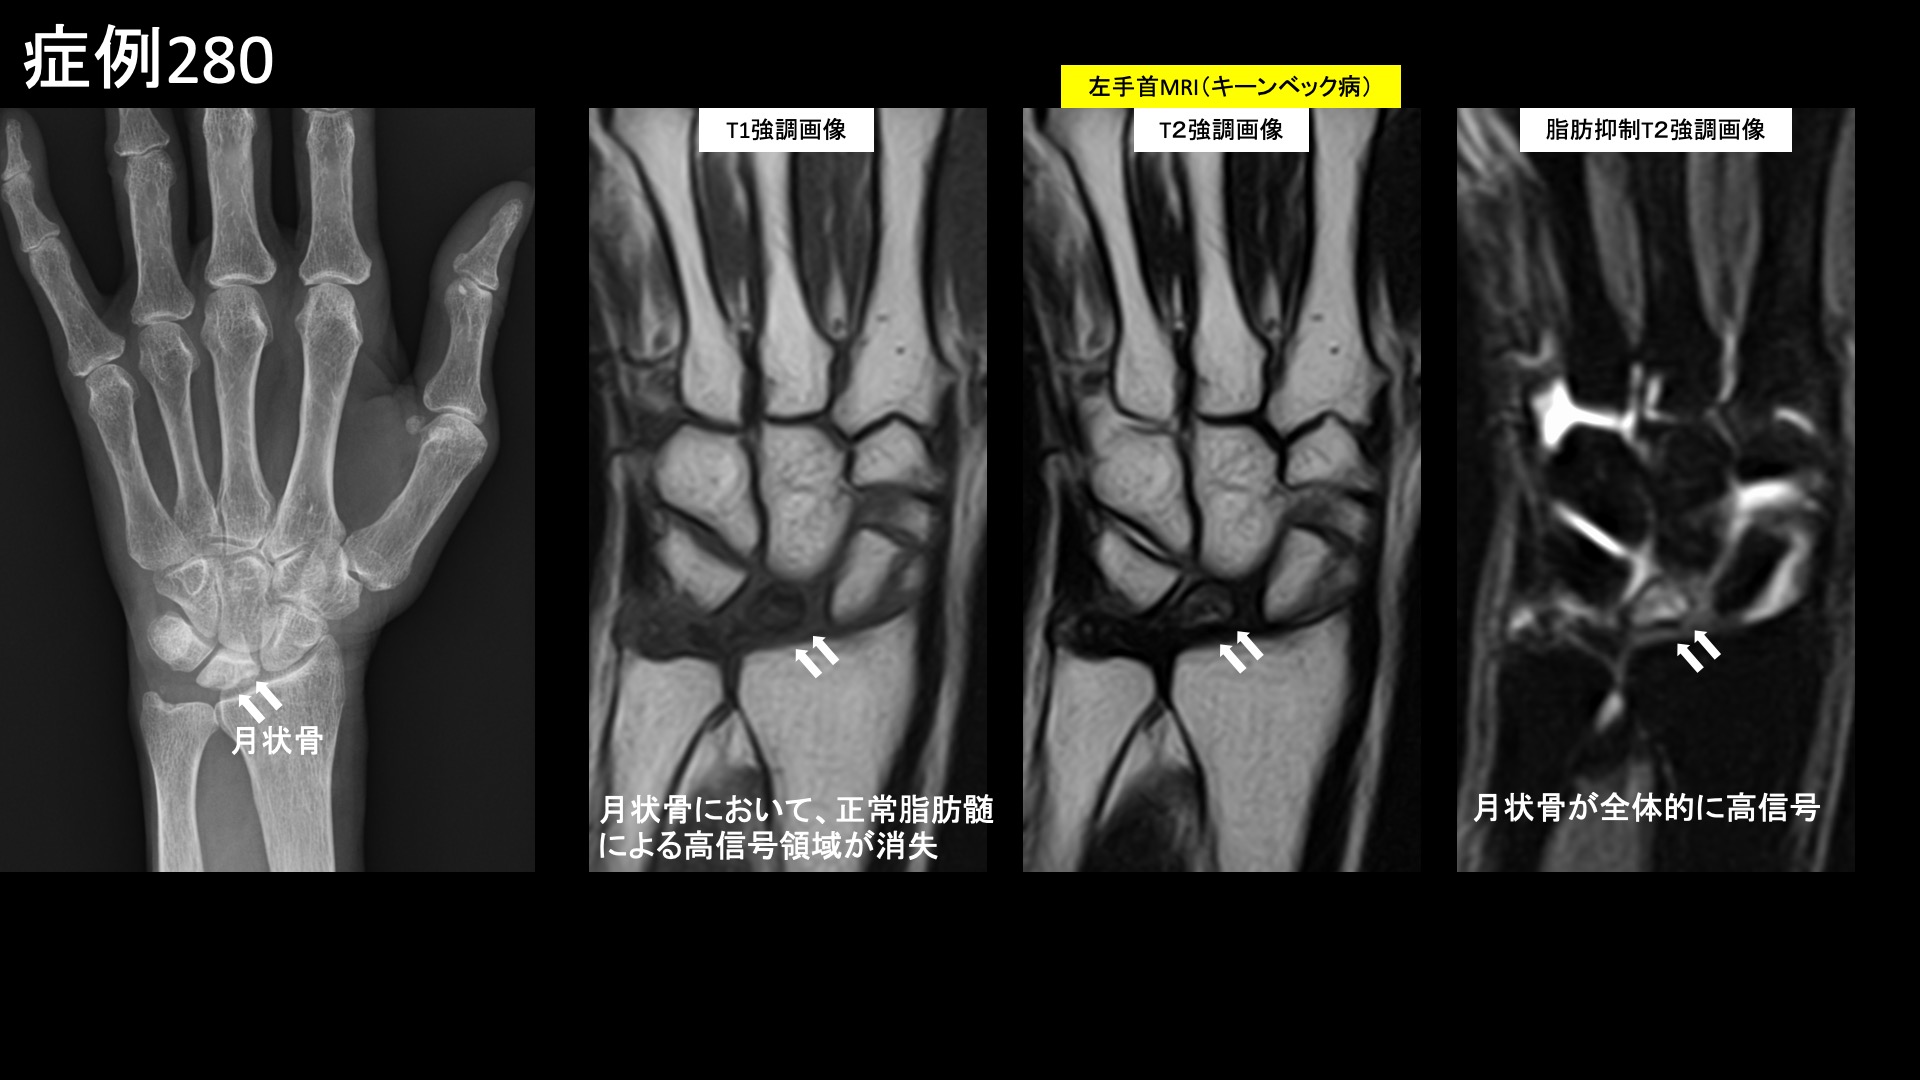

前医のMRI検査では、T1強調画像で低信号、脂肪抑制T2強調画像で高信号を認めており、キーンベック病の診断でしたが、病期としては保存的治療が可能な範囲でした。治療適応と判断し、モヤモヤ血管(病的新生血管)に対する運動器カテーテル治療(微細動脈塞栓術)を受けていただきました。

キーンベック病は早期であれば保存的治療方針、進行すると外科手術適応となる疾患です。カテーテル治療は外科手術の代わりになるわけではありませんので、月状骨が扁平化して周囲の関節変形を伴うようになると、外科手術を行う必要が出てきますが、それまでの境界領域において、特に手関節の機能は保たれていて痛みのコントロールを何とかできればよいという段階においては有力な治療選択肢です。重要なのは早期に発見することです。早期ではレントゲンで異常を検出できません。手首の疾患の画像診断にはMRI検査が必須です。不調を感じたら我慢しすぎず、早めに精査を受けていただきたいと思います。